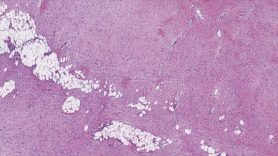

It takes an expert pathologist to tell the difference between scar tissue and a desmoid tumor. But expertise and experience from multiple disciplines are required for optimal outcomes.